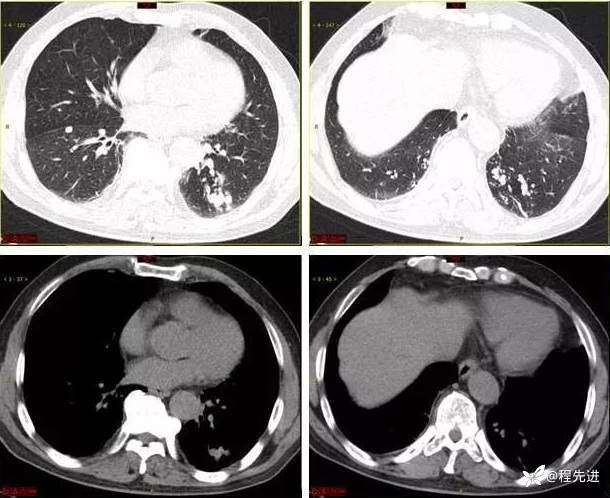

9月特别精彩病例|咳嗽伴咯血4月余,重点讨论胸部|结果已公布

患者性别:男

患者年龄:65岁

主诉:咳嗽伴咯血4月余

现病史:患者4月余前劳动后出现咳嗽,为阵发性干咳,以中午为主,后出现咯血,呈鲜红色,共5-6次,量最多时约50ml,约有3-4次。外院予以对症治疗(具体不详)后好转,1周前患者又出现咯血一次,约10ml。患者病程中无发热,时有胸闷,无胸痛,无呼吸困难,无盗汗,无恶心呕吐,无呕血黑便,食欲睡眠可,二便正常,体重无明显下降

有吸烟史30余年,2包/天,现戒烟10年,有饮酒史,半斤/天